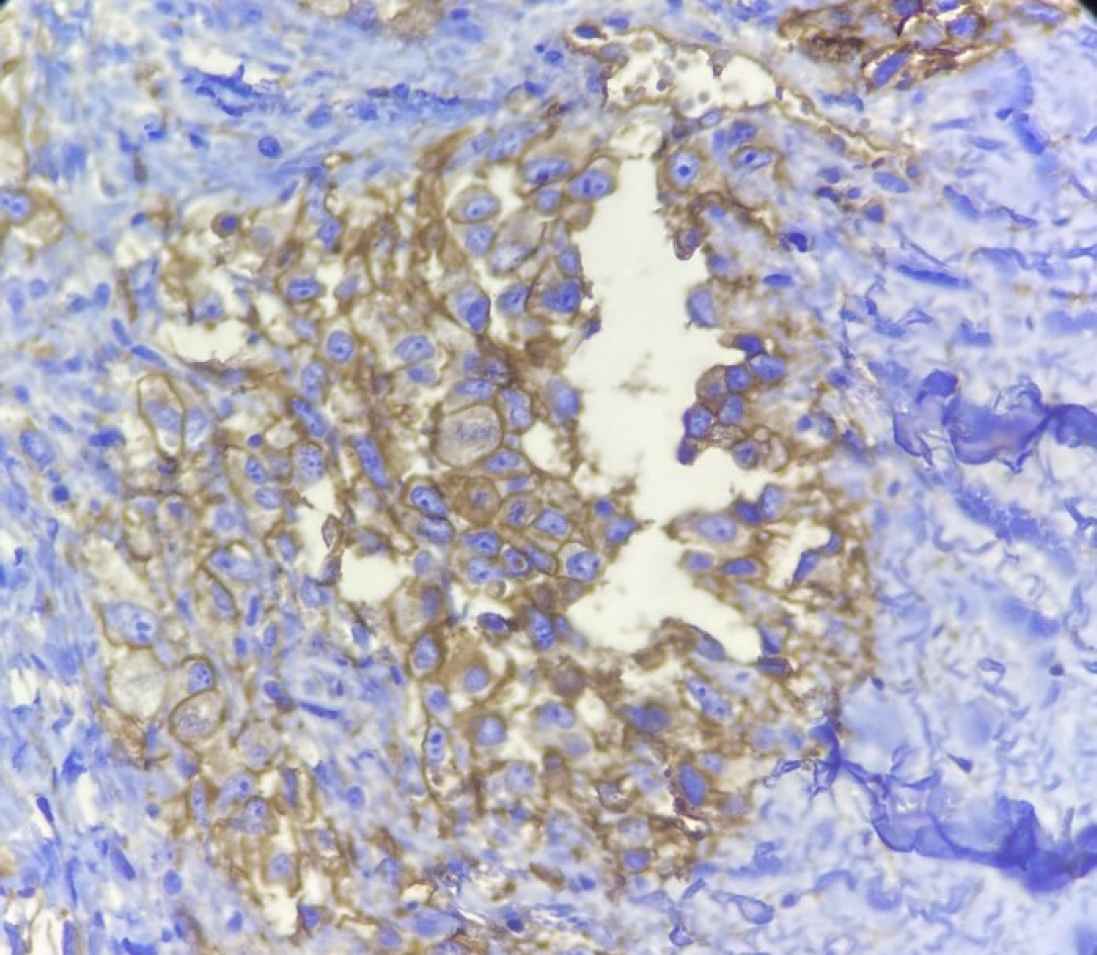

Macroscopically, the specimen was a 5× 2.5× 2 cm soft brown tissue with no identifiable mass lesion. Histopathologic examination showed polygonal cells and some spindle-shaped cells arranged around the intercommunication blood vessels. The solid areas of epithelioid anaplastic cells with large pleomorphic, vesiculated nuclei, prominent nucleoli and abundant mitotic activity were present (Figures 1 and 2). The vascular channels were lined by atypical spindle to plump cells. Some foci of hemorrhage and necrosis were also observed. Through immunohistochemical analysis, neoplastic cells demonstrated intense positive reactivity for CD31 and vimentin. Ki67proliferative index was 20% (Figure 3). A positive cytoplasmic immunoreactivity in tumor cells for WT1 was detected. Reactive mesothelial cells revealed positive nuclear staining for later marker in the same sections. Hence, the overall findings were consistent with pericardial angiosarcoma, epithelioid variant. After the operation, the patient received three cycles of chemotherapy with adriamycin, ifosfamide, and mesna. Unfortunately, she finally died of multiple pleural metastases and progressive cardiac invasion less than three months following the operation.

Fig. 3.Immunohistochemical staining for CD31 marker. (Objective 40x). Tumoral cells show cytoplasmic and membranous positivity for CD31